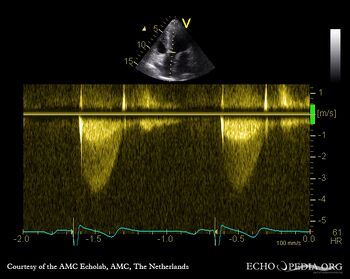

PSAX: Color Doppler, mild excentric aortic regurgitation Continuous-wave signal of transaortic flow: aortic bicuspid valve stenosis